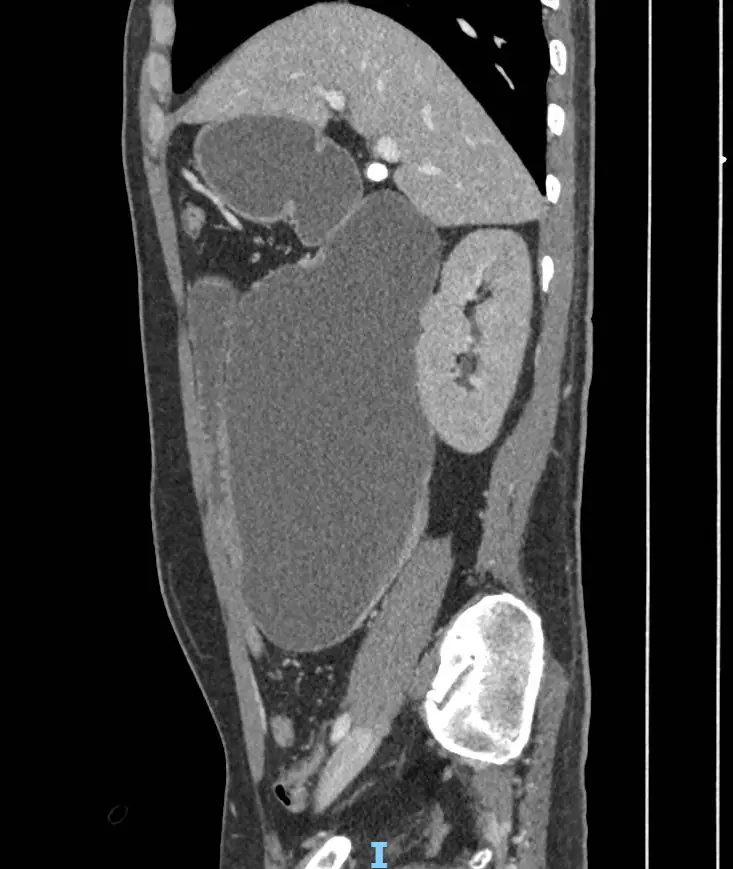

Anh Y.C.S. (42 tuổi, Campuchia) nhập viện FV trong tình trạng nguy kịch: nôn ra máu, sốc do thiếu máu và thiếu dịch, cơ thể suy kiệt, bụng chướng to bất thường. Kết quả CT scan khiến các bác sĩ kinh ngạc: dạ dày, tá tràng đã giãn cực đại, chiếm gần toàn bộ khoang bụng.

“Tá tràng là đoạn đầu tiên của ruột non, nối với dạ dày, dài khoảng 25cm. Ở người bình thường, tá tràng trong trạng thái xẹp, kích thước to chừng ngón tay, khi thức ăn đi vào thì giãn ra bằng đầu ngón chân cái. Riêng bệnh nhân này, khẩu kính tá tràng đo được có đường kính 12cm, chu vi 38cm, to bằng ống tay áo”, bác sĩ Thái cho hay.

Một dấu hiệu khá lạ và có ý nghĩa ghi nhận trong quá trình theo dõi ở ca bệnh này, đó là dạ dày đã xẹp và co lại rõ rệt sau khi đặt ống thông mũi – dạ dày – tá tràng 3 ngày, nhưng tá tràng thì không. Tá tràng vẫn giãn cực đại, dính vào các cơ quan xung quanh, gần như chiếm trọn không gian nội tạng phần bụng chậu và mất hoàn toàn chức năng co bóp.

Hình ảnh chụp cắt lớp vi tính: tá tràng giãn khổng lồ chiếm gần hết khoang bụng

Hình ảnh chụp cắt lớp vi tính: tá tràng giãn khổng lồ